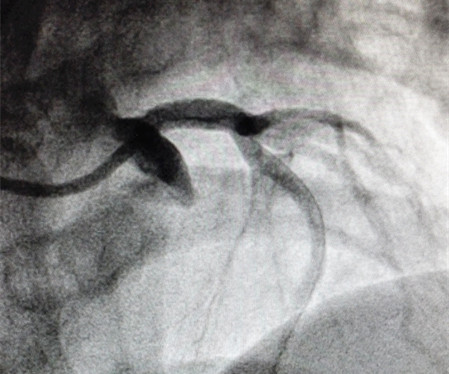

然而冠心病远非我们想象的那么简单,这位44岁的女性患者就是很好的例证。该患者主因“反复右侧胸痛”6月入院;既往身体健康;否认吸烟、高血压病及糖尿病等易患因素;该患者曾在多地药物治疗,效果不明显遂就诊于我院,入院后进行冠脉造影检查,结果提示左主干开口99%狭窄,左主干血管粗大。患者的造影结果超出所有人的预判,如果不采取介入或外科干预治疗,随时有发生猝死的风险。对于这种严重狭窄的左主干开口病变,国内外介入指南均列为高危复杂的病变,如果术中出现导管崁顿或支架贴壁不良,就有可能产生严重的恶性不良事件,许多医院只能选择外科冠脉搭桥手术;如果想通过微创介入处理该病变,往往需要血管内超声的帮助,还需要介入医师丰富的经验及过硬的胆识。对于该年轻患者,考虑到外科搭桥可能对患者造成的创伤大、术后恢复时间长等因素,张再伟博士还是建议对其进行介入治疗。在与患者家属沟通手术风险后,家属表示理解并愿意积极配合治疗,这给了张再伟博士极大的信心,遂于7月27日成功为患者实施介入手术,在左主干开口植入1枚支架,复查造影效果令人满意,患者症状明显好转,术后3天康复出院。

(手术后)